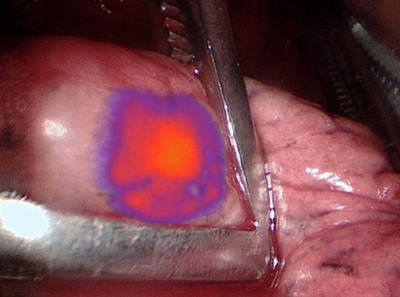

IMI with OTL38 illuminates lung nodules seen on PET/CT to give surgeons a better view. Image courtesy of Dr. Jarrod Predina et al and University of Pennsylvania Perelman School of Medicine.Based on the total number of 75 nodules seen by the two modalities, intraoperative molecular imaging was more accurate by detecting 68 nodules (91%), compared with 51 nodules (68%) seen on PET. Thus, sensitivity for IMI (95.6%) outpaced PET (73.5%) (p = 0.001), and IMI also achieved greater positive predictive values (94.2%), compared with PET (89.3%) (p > 0.05).